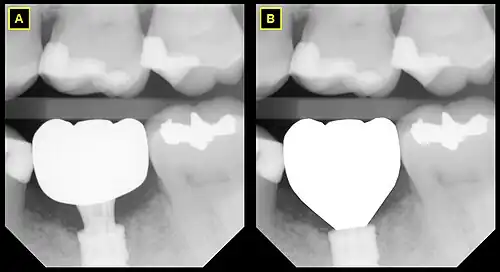

B This emergence profile respects the gingival architecture and emerges fully subgingivally.

In implant dentistry, running room refers to the apico-coronal distance between the platform of a dental implant and the gingival margin. It is a critical factor in restorative implant dentistry because it is effectively the "vertical distance [available subgingivaly] to make a transition from the smaller diameter prosthetic platform of an implant to the larger cross-sectional cervical shape of the tooth being restored."[1] The term was coined by Jonathan Zamzok, a Manhattan prosthodontist, in the late 1990s.[2]

As the anatomical crown and root tapers towards the apex, the mesial-distal dimension decreases, and so the mean mesial-distal dimension at the marginal crest of bone, which lies approximately 2 mm apical to the CEJ, is smaller. The tooth has the apico-coronal distance from the marginal crest of bone to the contact point in order to increase from the much narrower mesial-distal dimension to the greater mesial-distal dimension, and this distance is subgingival (below the gum line). Running room refers to this subgingival apico-coronal distance.